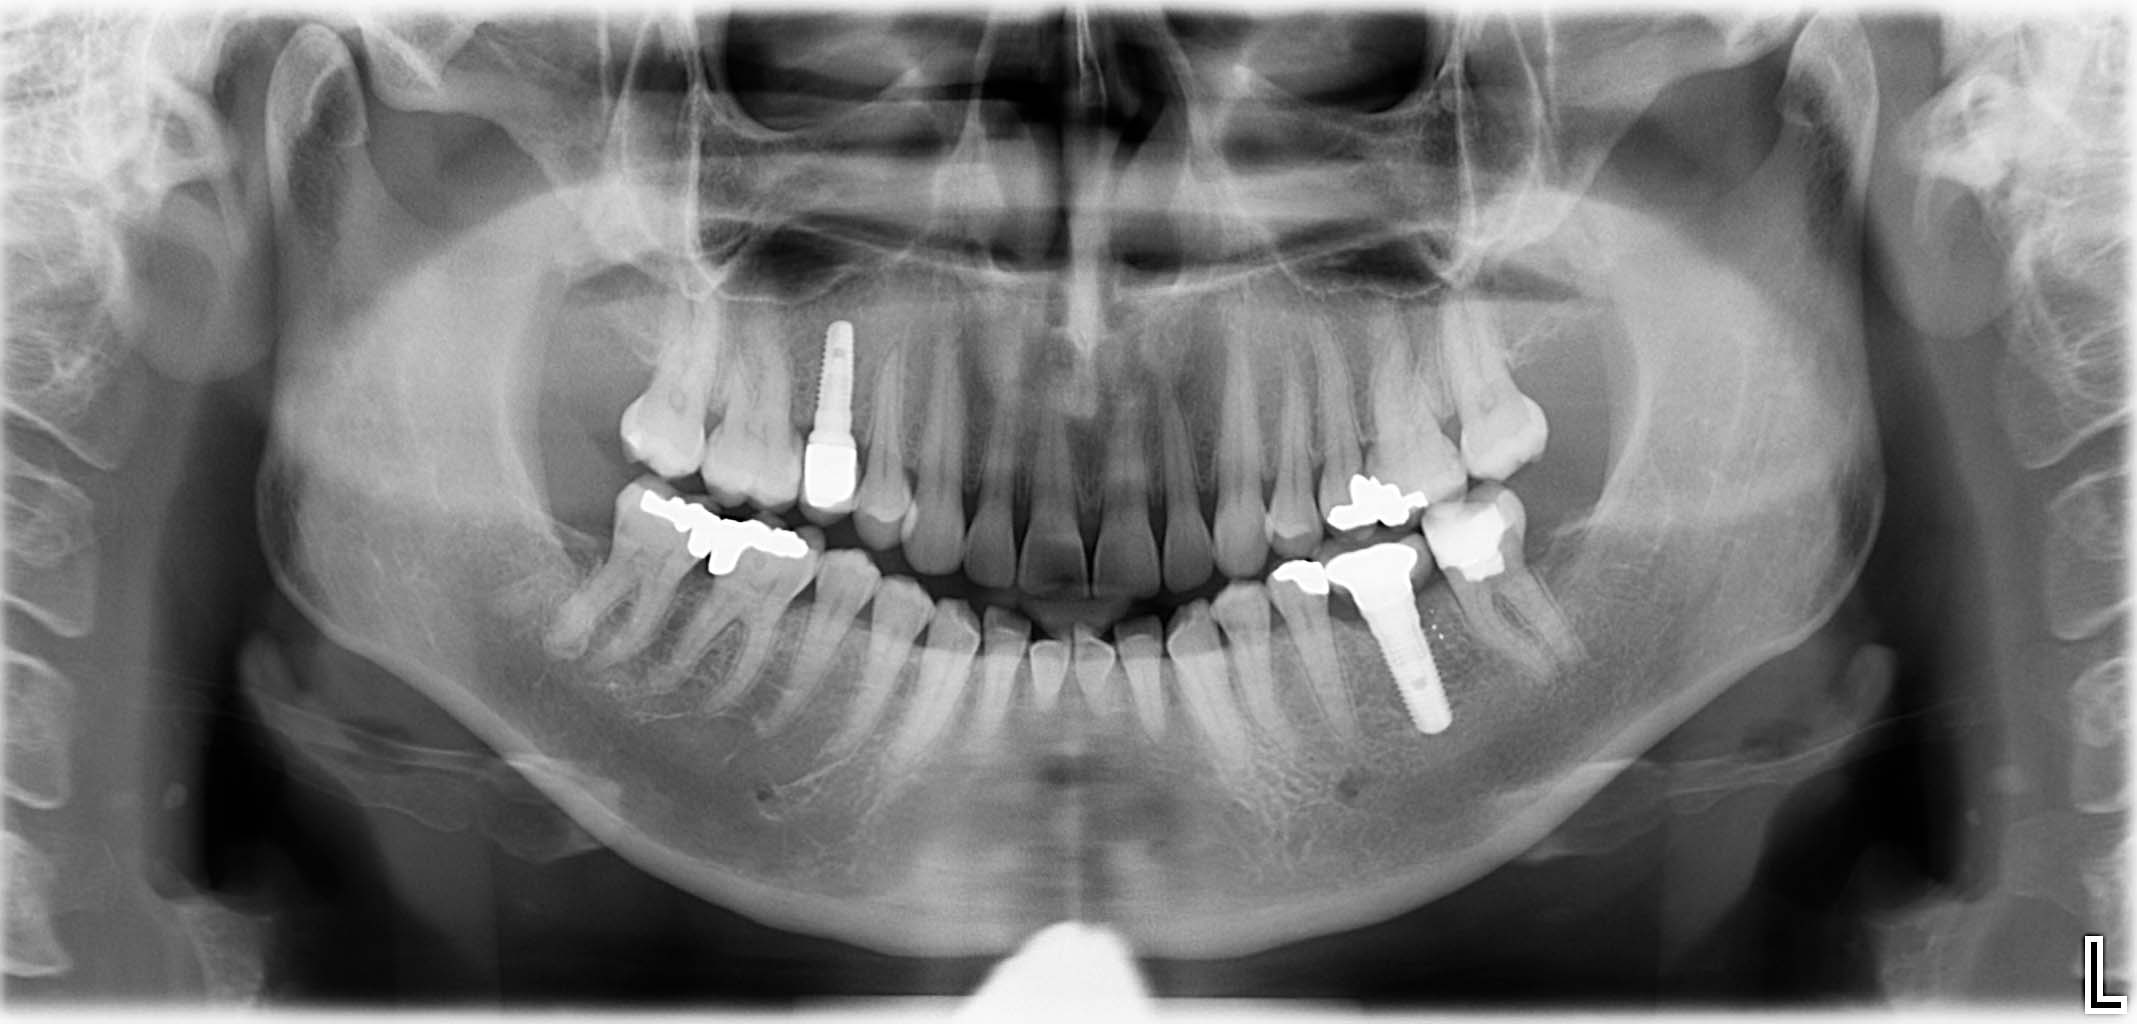

Erfolgreich implantierte Patientenfälle (klinische Fotos)